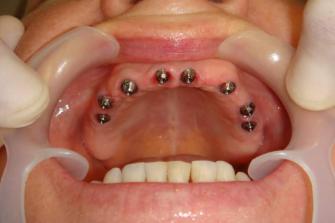

Implante Dentário Tipo Protocolo

O implante dentário tipo protocolo é muito usado nos dias atuais, pois tem inúmeras vantagens. A maior delas é o paciente deixar de usar uma prótese móvel (dentadura).

Implante Dentário Protocolo é um procedimento cirúrgico e protético onde é feito a colocação dos implantes e a prótese fixa sobre os implantes. A prótese pode ser confeccionada em acrílico ou em cerâmica.

Para ser feito a protocolo, é necessário o profissional especializado fazer a colocação de diversos implantes, variando superior na maxila de seis implantes (parafusos) e inferiores na mandíbula quatro implantes (parafusos).

Após o tempo de cicatrização é colocado à prótese parafusada sobre os implantes.